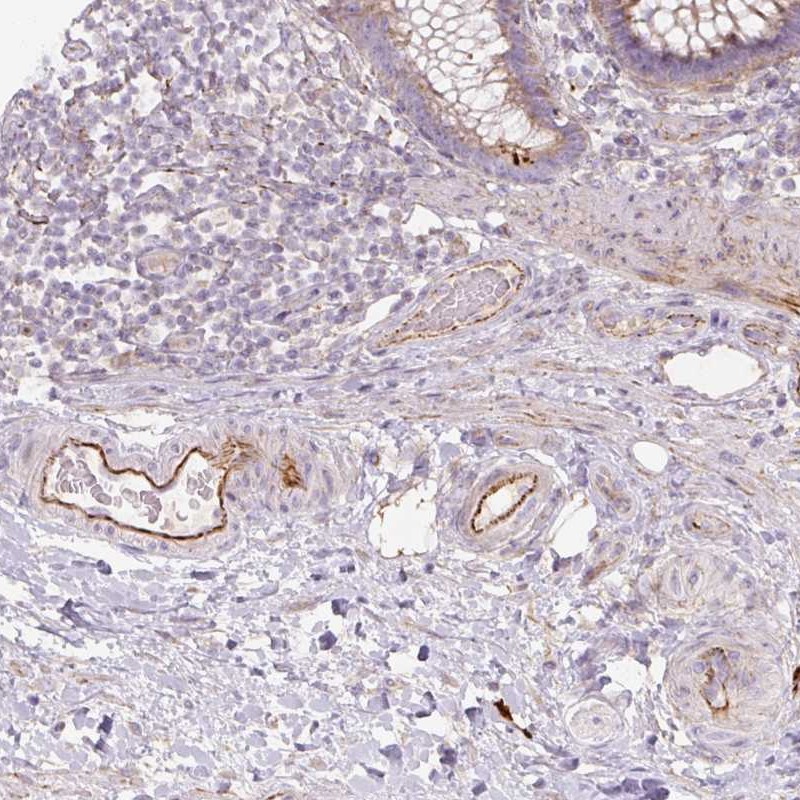

Immunohistochemical staining of human colon shows strong positivity in endothelial cells.